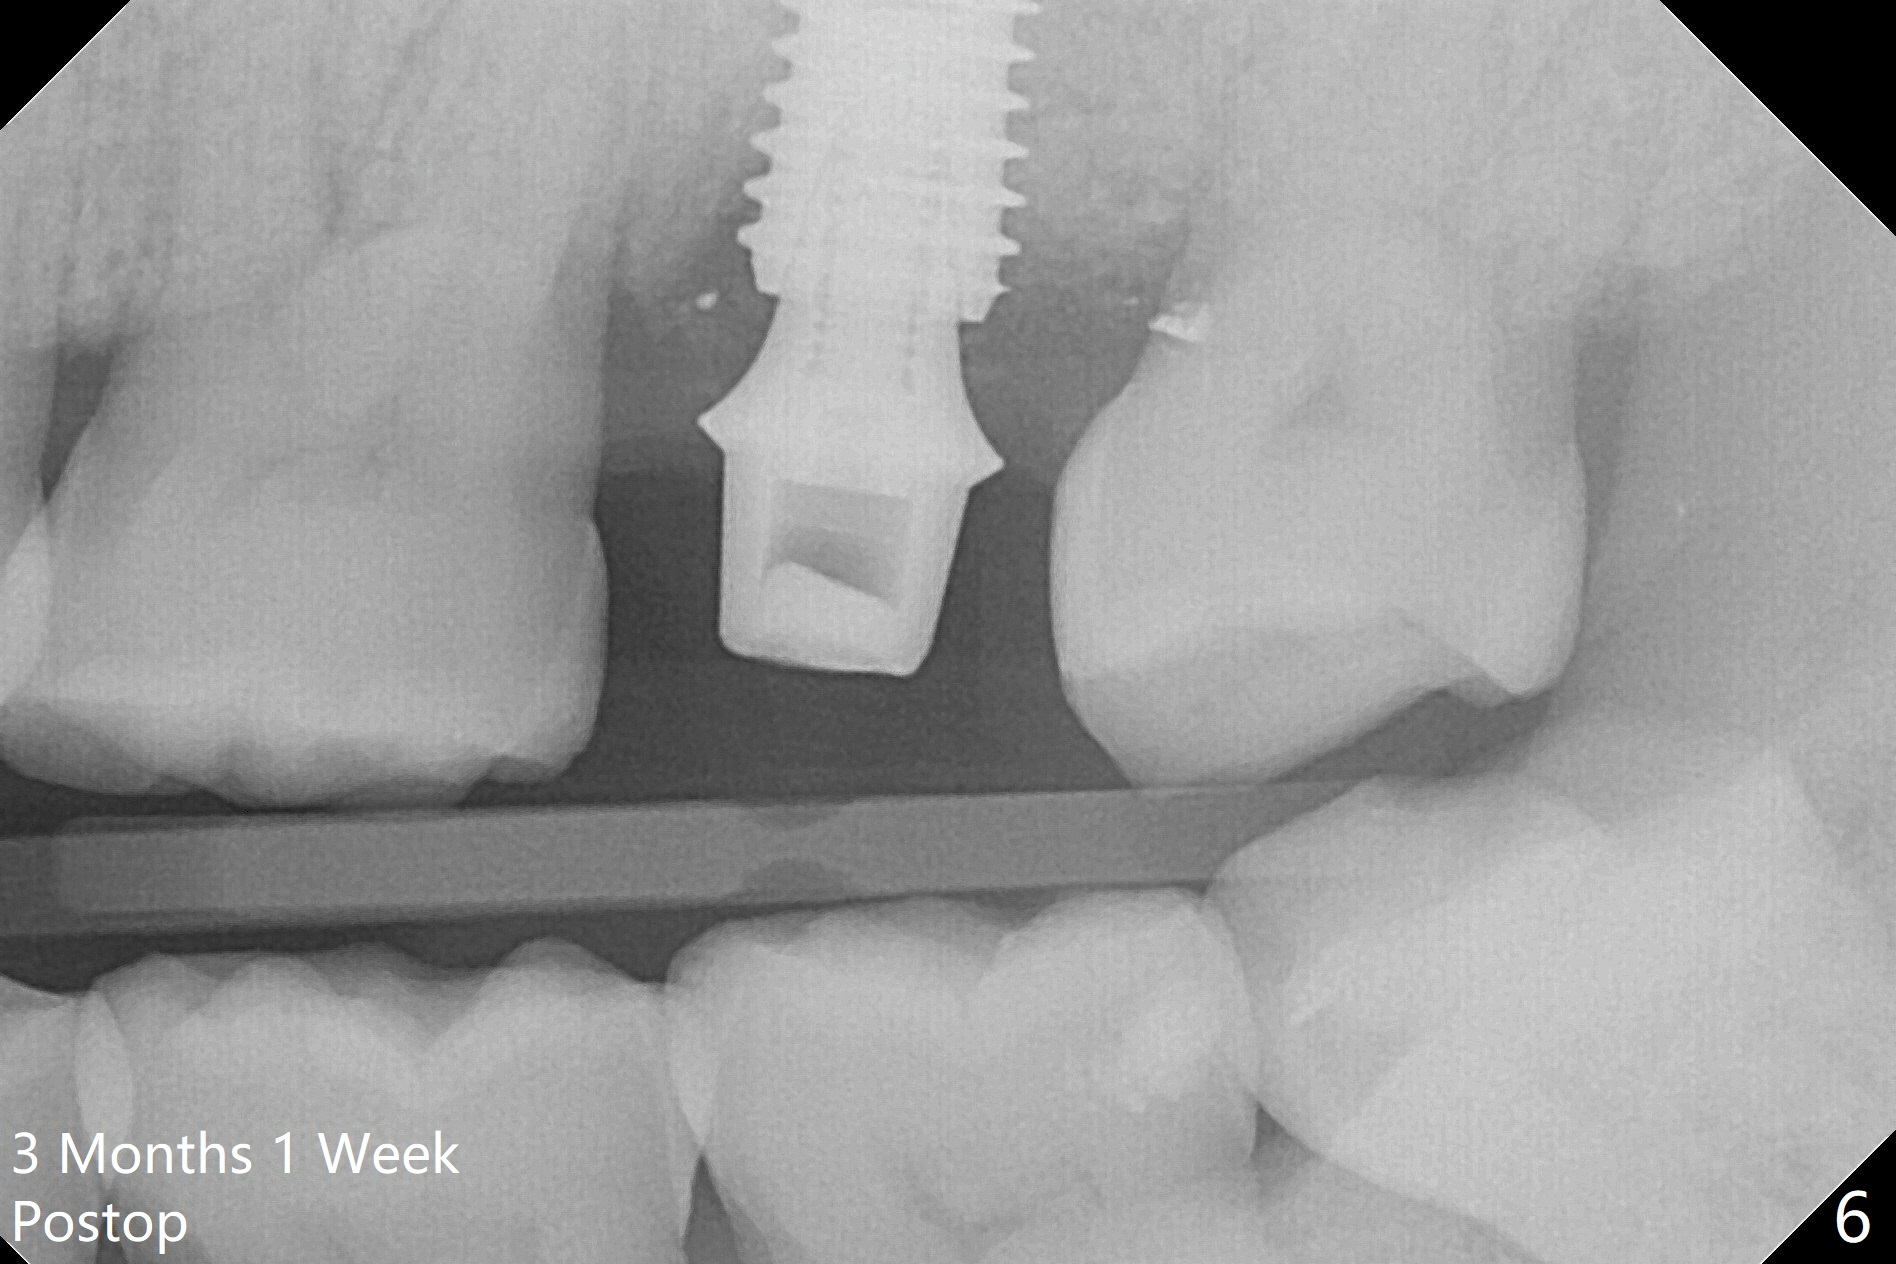

When the patient returns for the tooth #15 extraction and implant, the mesiobuccal residual root has been expelled, while the distobuccal and palatal roots seem to have extruded (Fig.1). The mesial portion of the gingiva (G) is intact and thick. The trajectory of the initial osteotomy is to be changed as shown by red line in Fig.2. The 3.8 mm drill appears to be distal (Fig.3). With mesial bone removal with Lindamann bur, the position of the final implant (5x13 mm) is within normal limit (Fig.4 (50 Ncm)). Because of the thick mesial gingiva (Fig.4 G) and placement of the 5.5x4(2) mm abutment, insertion of mixture of autogenous and Vanilla Graft (*) into the mesial aspect of the implant is difficult (Fig.4 >). Further pushing of the bone graft from the buccal and palatal socket gaps results in more ideal packing (Fig.5 >). If the bone graft were placed first, packing would have been easier. An immediate provisional is fabricated to prevent further mesial shifting of the 3rd molar (Fig.1 arrow). The implant remains stable, while the provisional and abutment are loose 3 months 1 week postop (Fig.6). Impression is taken after abutment cleaning and retightening. Because of the long implant (13 mm), a permanent crown can be cemented early (3 months 20 days postop, Fig.7).